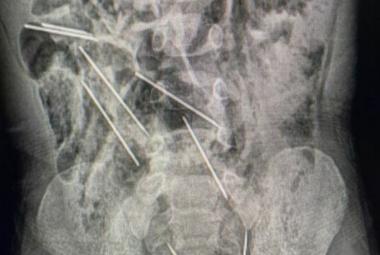

Dječak hitno prebačen u bolnicu: Progutao osam medicinskih igala, odmah operisan

Aktuelnosti

Wed, 13 Sep 2023 - 09:25